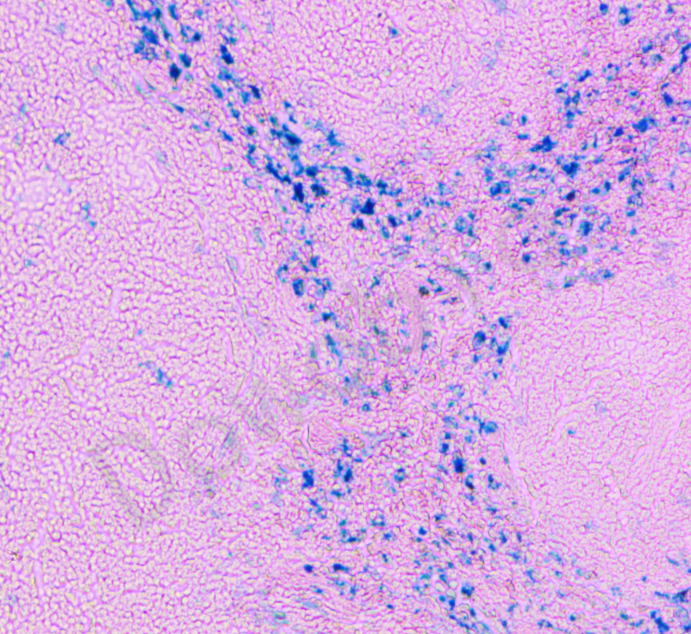

普鲁士蓝铁染色法(Perl's Iron Stain)是检测细胞和组织中非血红素铁的常用组织化学方法之一,通过形成蓝色的普鲁士蓝沉淀检测骨髓及肝、脾、肾等组织细胞中的铁蛋白和含铁血黄素沉积。

含铁血黄素呈蓝色,其他组织呈复染颜色。